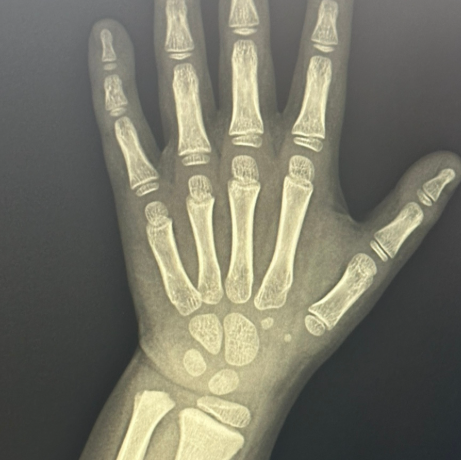

손 뼈 촬영 (골연령 검사) ✋ → 뼈 나이와 실제 나이 비교

✅ 골연령: 7세 (실제보다 1년 늦음)

→ 손뼈 촬영은 1년에 2회 정도 진행하면 충분하다고 하셨어요.